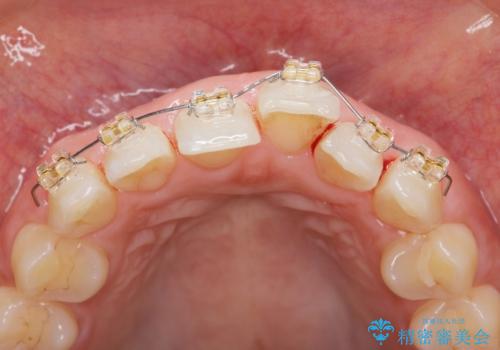

前歯のガタつきをきれいに マウスピース矯正治療

- 「前歯のガタつきをきれいにしたい。」と矯正治療を希望され来院されました。

前歯のガタつきをワイヤー部分矯正、上顎前突の咬合関係を後方移動することで理想的な咬合関係を確立します。

上顎の全体的な後方移動を実現するためにマイクロインプラントを併用したゴムかけを行ったことで理想的な咬合関係を確立することができました。